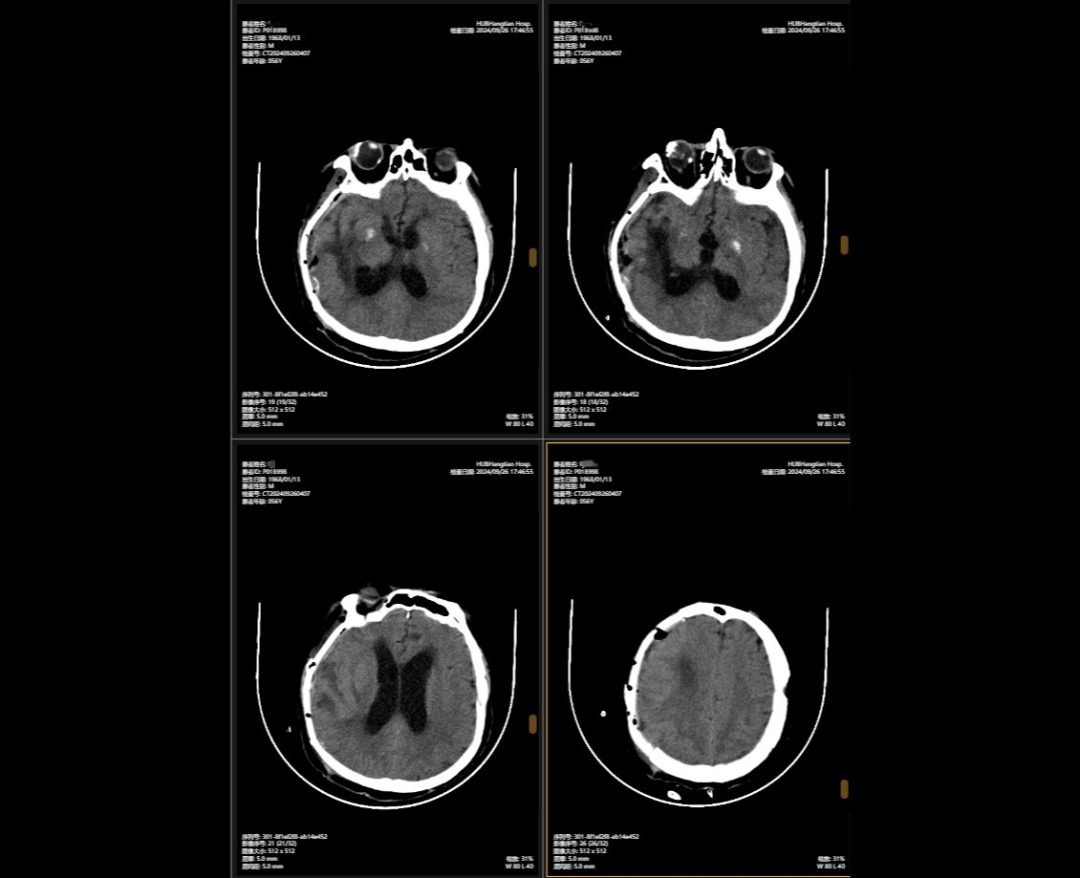

顱骨缺損修補(bǔ)術(shù)前術(shù)后對(duì)比

李先生的病情穩(wěn)定后,神外團(tuán)隊(duì)緊繃了數(shù)周的神經(jīng)終于得以松弛,他們隨即為他制定了顱骨缺損與腦積水治療方案,2024年9月,李先生接受了顱骨缺損修補(bǔ)術(shù),“修補(bǔ)”之前取下的頭骨,保護(hù)大腦,解決顱內(nèi)壓力不穩(wěn)問(wèn)題,術(shù)后他的神經(jīng)紊亂癥狀明顯改善;三個(gè)月后,神外團(tuán)隊(duì)繼續(xù)施行腦室-腹腔分流術(shù),通過(guò)植入的分流管,解決了腦積水問(wèn)題,讓腦壓恢復(fù)正常。